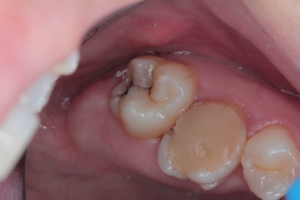

Приклади робіт лікаря-стоматолога

Естетична реставрація. До / після